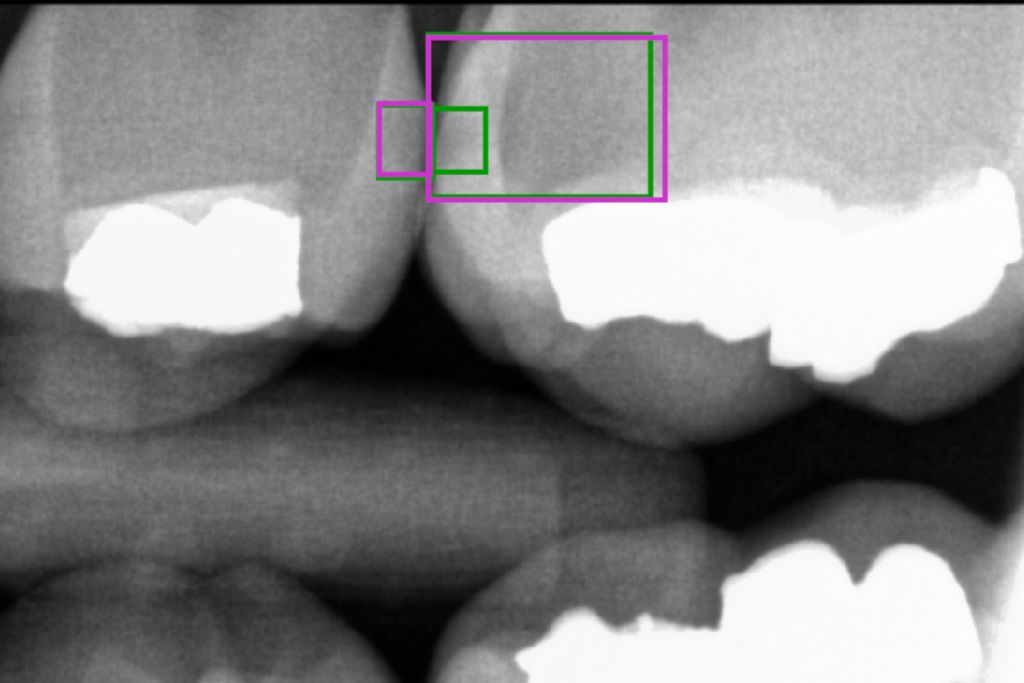

Čeští vědci našli způsob, jak s pomocí umělé inteligence spolehlivěji odhalit zubní kazy